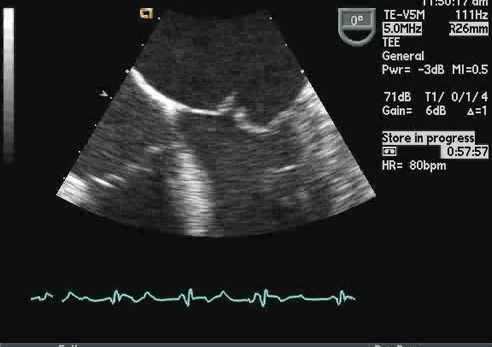

Обструкция протеза на эхокардиографии

Заболеваемость обструкции протезированных клапанов оценивается в 0,1% до 0,4% в год, в зависимости от размера клапана, его типа, расположения и адекватности антикоагуляции. Тогда как обструкция митрального механического протеза возникает чаще от тромба, причиной сужения механического протеза аортального клапана более часто является формирование паннуса. Когда работа протезированного клапана будет затруднена, происходит нарушение движения диска, шара, или уменьшается подвижность створки. Однако, это трудно выявить эти ситуации, и еще труднее оценить количественно, ограничение экскурсии на простой трансторакальной эхокардиографии. Чреспищеводная эхокардиография может в состоянии визуализировать нормальные и патологические движения протезированного клапана. Самый точный способ для выявления и количественной оценки степени обструкции протезов является допплер-эхокардиография. Допплеровское исследование должны быть выполнены датчиком с различных позиции, чтобы гарантировать, что фиксируется максимальная скорость в месте стриктуры протеза.

Тромб. Чаще встречается в механических клапанах и отвечает за многие случаи неисправности протеза. Это может произойти, если контроль антикоагуляции плохой или при наличии расширенных камерах сердца. Антикоагуляция необходима для всех механических клапанов (стремитесь к международному нормализованному отношению [МНО] 3,5-5,0). Восприимчивость протезов клапанов к тромбозу зависит от их положения (связанного с градиентом давления на клапане). Иногда пациенты жалуются, что больше не слышат щелчки клапана — это может быть признаком тромбоза.

ЭхоКГ может обнаружить тромб с помощью:

- Визуализации подвижного образования на клапане - ее бывает сложно отличить от вегетаций или кальцинированных узелков

- Уменьшение или отсутствие движения подвижной части клапана (например, шара, диска, створок)

- Сопутствующее расширение камер сердца.

- Как и в случае с вегетациями, в M-режиме может отображаться несколько темных эхо-линий и / или уменьшенное открытие или закрытие клапана. Допплерография и ЦДК могут указывать на препятствие для открытия клапана (повышенная скорость потока) или препятствие для закрытия (новая чресклапанная регургитация или увеличение степени тяжести существующей регургитации).

Лечение тромба механического клапана зависит от его тяжести и гемодинамических последствий. Пациенты с признаками обструкции клапана обычно страдают от нарушенной сердечной гемодинамики и традиционно нуждаются в срочной операции. В настоящее время тромболизис становится эффективной альтернативой. Тем, у кого нет признаков значительной обструкции, необходима агрессивная и требовательная антикоагулянтная терапия.